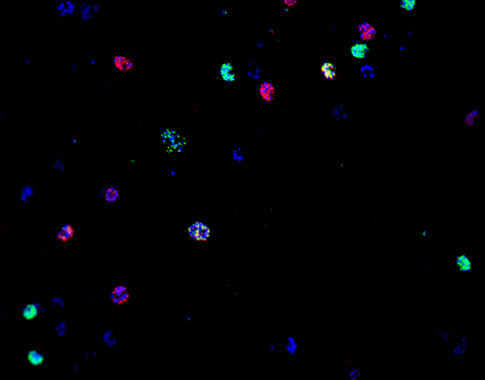

Sin embargo, un equipo liderado por Alfred Cortés (ISGlobal) y Anna Rosanas-Urgell (ITM) exploró el rol de la epigenética en la resistencia a antimaláricos. Se fijaron particularmente en dos genes del parásito –clag3.1clag3.2 – cuya expresión se regula por mecanismos epigenéticos y que determinan la actividad de un canal (llamado PSAC por sus siglas en inglés) que regula la entrada de nutrientes y otras moléculas en glóbulos rojos infectados por el parásito.

Previamente, Cortés y su equipo habían demostrado que cambios en la expresión de clag3 resultaban en cambios en la permeabilidad de PSAC y una mayor resistencia a compuestos tóxicos para el parásito. En este estudio, el equipo se preguntó si otros antimaláricos necesitan la expresión de clag3 para actuar sobre su diana intracelular y que por lo tanto pudieran estar sujetos a resistencias por mecanismos epigenéticos.

Encontraron que ciertos compuestos como las sales de tiazol T3 y T16 necesitan la expresión de los genes clag3 para penetrar en los glóbulos rojos infectados. Además, demostraron que las poblaciones de P. falciparum pueden desarrollar resistencia a estos compuestos mediante la selección de parásitos que han reducido la expresión de ambos genes. En cambio, otros compuestos como la doxiciclina, azitromicina o lumefantrina, que se cree penetran usando otras vías de transporte, no necesitan la expresión de clag3 para ejercer su actividad antimalárica.